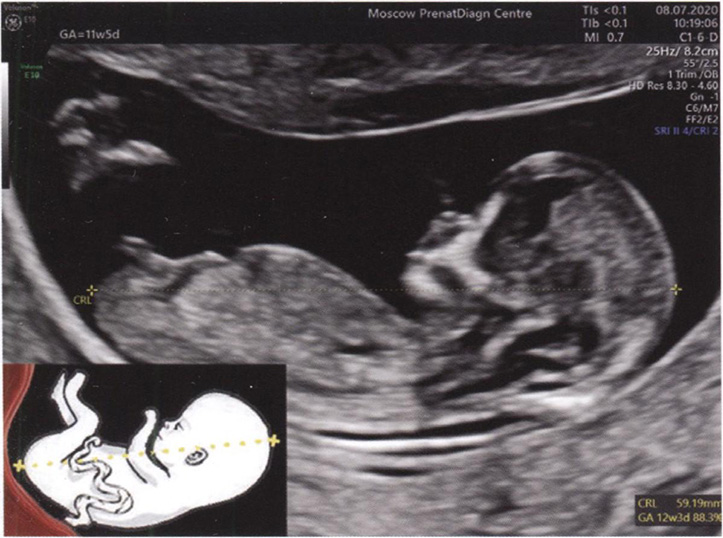

Копчико-теменной размер (КТР) - это максимальное расстояние по прямой линии от головного до тазового конца эмбриона/плода в мм (табл. 1. 2).

Правила измерения КТР плода (рис. 1. 2):

- увеличение изображения должно быть максимальным при условии четкой визуализации плода от головы до тазового конца;

- расположение плода — строго горизонтальное спинкой вниз; линия, соединяющая голову и копчик, должна быть параллельна плоскости сканирования;

- максимально точное сагиттальное сечение плода на всем протяжении — четко визуализируется кончик носа и позвоночник плода на всем протяжении;

- нейтральное положение плода (затылочная кость является как бы продолжением позвоночника и расположена с ним на одной воображаемой линии).

Рис. 1.2. Эхограмма и схема измерения КТР плода